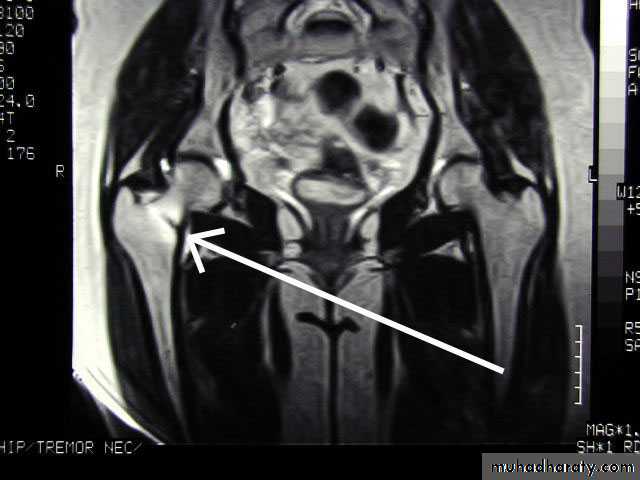

39Pathlogical fracture

# that occurs with trivial trauma in a bone weekened by a pathologic process

e.g. osteoporosis, Paget`s d.,infection, & tumours